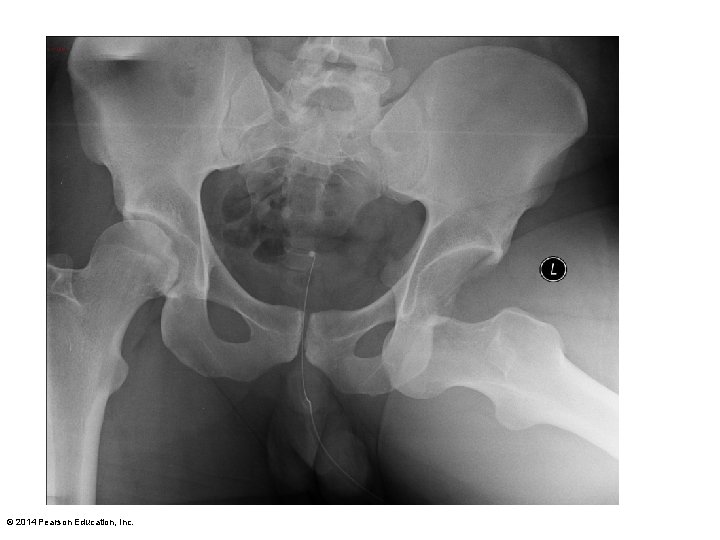

Figure 8. 12 The hip joint. Acetabular labrum Coxal (hip) bone Articular cartilage Acetabular labrum Ligament of the head of the femur (ligamentum teres) Synovial membrane Femur Ligament of the head of the femur (ligamentum teres) Head of femur Articular capsule (cut) Synovial cavity Articular capsule Frontal section through the right hip joint Photo of the interior of the hip joint, lateral view Iliofemoral ligament Ischium Ischiofemoral ligament Greater trochanter of femur Posterior view of right hip joint, capsule in place © 2014 Pearson Education, Inc. Anterior inferior iliac spine Iliofemoral ligament Pubofemoral ligament Greater trochanter Anterior view of right hip joint, capsule in place

Figure 8. 12 b The hip joint. Acetabular labrum Synovial membrane Ligament of the head of the femur (ligamentum teres) Head of femur Articular capsule (cut) Photo of the interior of the hip joint, lateral view © 2014 Pearson Education, Inc.